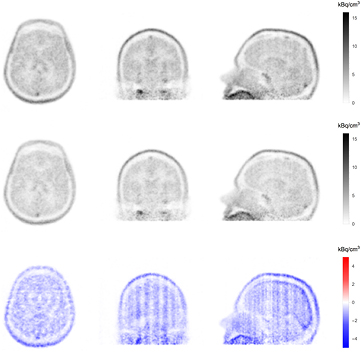

We computed the difference images between ground truth (image measured without coil and reconstructed without coil AC) and the images acquired with the Tx/Rx head coil and reconstructed them with different coil attenuation corrections (no coil AC, standard-coil-AC, and Lu-coil-AC). The reconstructed voxel size for all images was  and the difference images are shown in figure 11. As expected, the difference between ground truth and image acquired with the Tx/Rx head coil, but without coil AC, shows streaks due to uncorrected γ attenuation. Moreover, a negative bias of up 7 kBq

and the difference images are shown in figure 11. As expected, the difference between ground truth and image acquired with the Tx/Rx head coil, but without coil AC, shows streaks due to uncorrected γ attenuation. Moreover, a negative bias of up 7 kBq  (hot compartment VOI) was observed. When using the standard-coil-AC method, streaks due to γ attenuation by the coil are reduced, but a positive bias of up to 6 kBq

(hot compartment VOI) was observed. When using the standard-coil-AC method, streaks due to γ attenuation by the coil are reduced, but a positive bias of up to 6 kBq  (hot compartment VOI) is observed. When using the Lu-coil-AC method, streaks are further reduced but a negative bias is still present. However, the maximum bias is 4 kBq

(hot compartment VOI) is observed. When using the Lu-coil-AC method, streaks are further reduced but a negative bias is still present. However, the maximum bias is 4 kBq  , which is significantly smaller than for the other two cases.

, which is significantly smaller than for the other two cases.

Figure 11. Difference emission images of a single slice of the three compartment phantom. Left: Difference between ground truth and image without coil AC. Middle: Difference between ground truth and image with standard-coil-AC. Right: Difference between ground truth and image with Lu-coil-AC. Ground truth is data acquisition without coil and reconstruction without coil AC.

Standard image High-resolution imageAnalysis of the volumes of interest showed that, except for the VOI in the surrounding air and the background compartment, the mean activity concentration for the Lu-coil-AC best approaches the mean activity concentration of the ground truth. Mean values obtained using the standard-coil-AC always overestimated the ground truth values. Without coil AC, the activity concentrations in the hot, cold, and background compartment were underestimated, whereas the activity concentrations in the PTFE compartment and the surrounding air were overestimated. Standard deviation and coefficient of variation were highest for Lu-coil-AC, which was expected because of the low 176Lu activity. Mean values, differences of mean values to the ground truth, standard deviation and coefficient of variation for all VOIs and all 4 reconstructions are given in table 3. Corresponding Box–Whisker plots are shown in figure 12.

Image reconstructions comparing standard-coil-AC to Lu-coil-AC for the three subjects are shown in figures 13 and 15. Figures from an additional FDG exam are provided in the supplementary data (stacks.iop.org/PMB/63/035039/mmedia). In all three cases, faint streak artefacts that are visible in the images with standard-coil-AC are slightly reduced by using Lu-coil-AC. This is noticed, in particular, for the image reconstruction of the FET examination (figure 13). The different strengths of the weak streak artefacts and their location in the image can be easily seen in the corresponding difference images. The difference images are overlaid by the concentric ring artefacts previously mentioned, e.g. Badawi and Marsden (1999) and references therein, and are apparently not a consequence of the attenuation correction methods used. The concentric ring artefacts are not discerned in the transversal slices of the head and phantom images. Figure 14, left, shows the same image as figure 13, bottom left, but with a modified colour range and overlay of the head coil CT image for better visualisation and localisation of residual artefacts. For comparison, the difference between the ground truth phantom image and the phantom image with the coil but without coil AC is shown in figure 14 to the right (averaged over all image planes). A further important observation is that the estimated activity concentration is systematically higher for image reconstruction with the standard-coil-AC than for reconstructions with the Lu-coil-AC. The slightly increased image noise, as expected from table 3, is hardly noticeable in the head images reconstructed with the Lu-coil-AC. These three observations are in agreement with the findings in section 3.4. Except for the bias of the activity concentration, which can be compensated by recalibration of the Siemens 3T MR-BrainPET insert with the Lu-coil-AC, the observed differences in both AC methods are too small to be clinically relevant.

Figure 13. Transversal slice (left), coronal slice (mid), and sagittal slice (right) of first subject (FET). Upper row shows images reconstructed with standard-coil-AC. Middle row shows images reconstructed with Lu-coil-AC. Lower row shows difference images between Lu-coil-AC and standard-coil-AC.